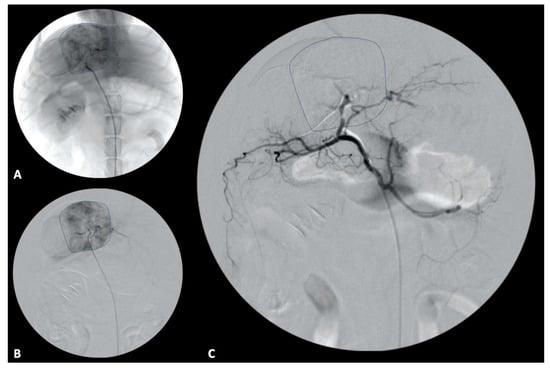

Surgical techniques for liver lobe tumors described in small animals include partial liver lobectomy, or total/hilar liver lobectomy. In dogs, there is a consistent single hepatic artery and biliary duct associated with each liver lobe although there may be multiples of portal and hepatic veins, highlighting the importance of a pre-operative CT scan (Figure 1) for appropriate planning [78]. Additionally, the length and location of the central hepatic vein in dogs is frequently prohibitive of an independent resection of the right medial or quadrate liver lobes, necessitating en bloc removal of the central division if either lobe is affected [78]. Surgical stapling and blunt dissection and ligation have been compared for hilar liver lobectomy, with both achieving similar outcomes regarding risk of hemorrhage, although the ligation technique had significantly increased surgical times compared to stapling [79]. Methods of partial liver lobectomy include stapling, blunt dissection and ligation, skeletonization and vascular clipping, use of energy devices (e.g., vessel-sealing device, ultrasonic devices), and pre-tied endoscopic loops. Increased risk of hemorrhage has been associated with skeletonization and vascular clipping when compared to the other techniques [80]. Leakage of surgical sites perfused with supraphysiologic pressures in dogs following partial liver lobectomy identified pre-tied ligature as the most secure vascular ligation, although none of the techniques listed above demonstrated leakage at physiologic pressures [80]. Clinically, a combination of techniques may be necessary to navigate the unique vascular and parenchymal anatomy encountered during hepatobiliary surgery for each patient (Figure 2).

Figure 1. Massive hepatocellular carcinoma arising from the right lateral liver lobe in an 8-year-old mixed-breed dog. The patient underwent right lateral liver lobectomy without complication. (A) Arterial phase CT image in axial plane of the right lateral liver hepatocellular carcinoma with the aorta (asterisk) and compressed caudal vena cava (plus sign) demarcated. (B) Arterial phase CT image in sagittal plane with the aorta (asterisk) and hepatic artery (caret) demarcated.